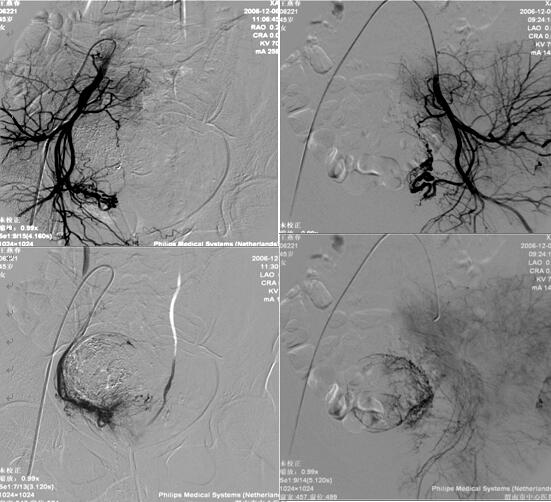

乐鱼在线登录入口介入科在李建国主任带领下自2006年开展子宫肌瘤栓塞术,现已完成数百例相关疾病介入治疗,为渭南地区及各县患者提供了全新的子宫肌瘤治疗方法,避免患者子宫全切。子宫肌瘤栓塞术是一种安全有效的治疗方法,是由介入医生经病人腹股沟股动脉导入一导管至肌瘤的血供(子宫动脉)处,释放一些细微颗粒,弹簧圈、或者球囊等阻断肌瘤的血供、供养及出血部位,使肌瘤纤维化,出血停止,肌瘤萎缩。所有经过介入治疗的患者术后大约3-6个月相关症状完全消失。

经子宫动脉栓塞术还可应用于子宫腺肌症、胎盘植入、瘢痕妊娠、前置胎盘及产后大出血等疾病,以下为一例产后大出血患者介入治疗图片: